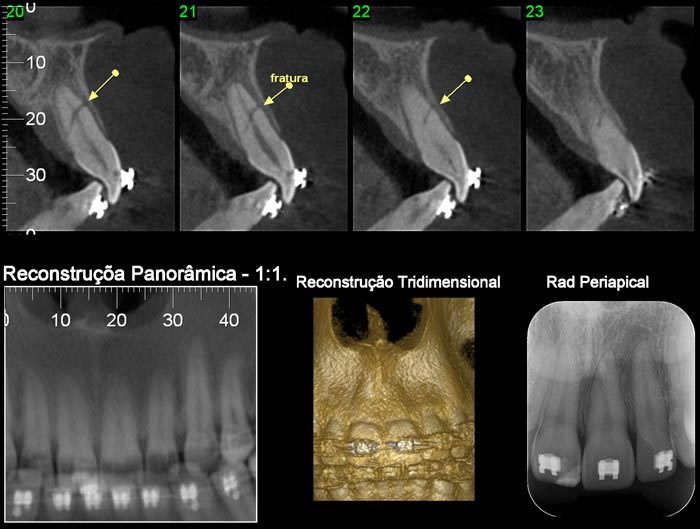

Caso 3: Fratura de ATM

Paciente com história clínica de trauma. Fratura no côndilo direito com deslocamento do fragmento para medial e deslogamento do côndilo para lateral da cavidade articular.

Caso 4: Lesão Patológica

O exame tomográfico permite a exata localização e extensão do tumor bem como a identificação de áreas com destruição da cortical e a localização de lesões satélites.